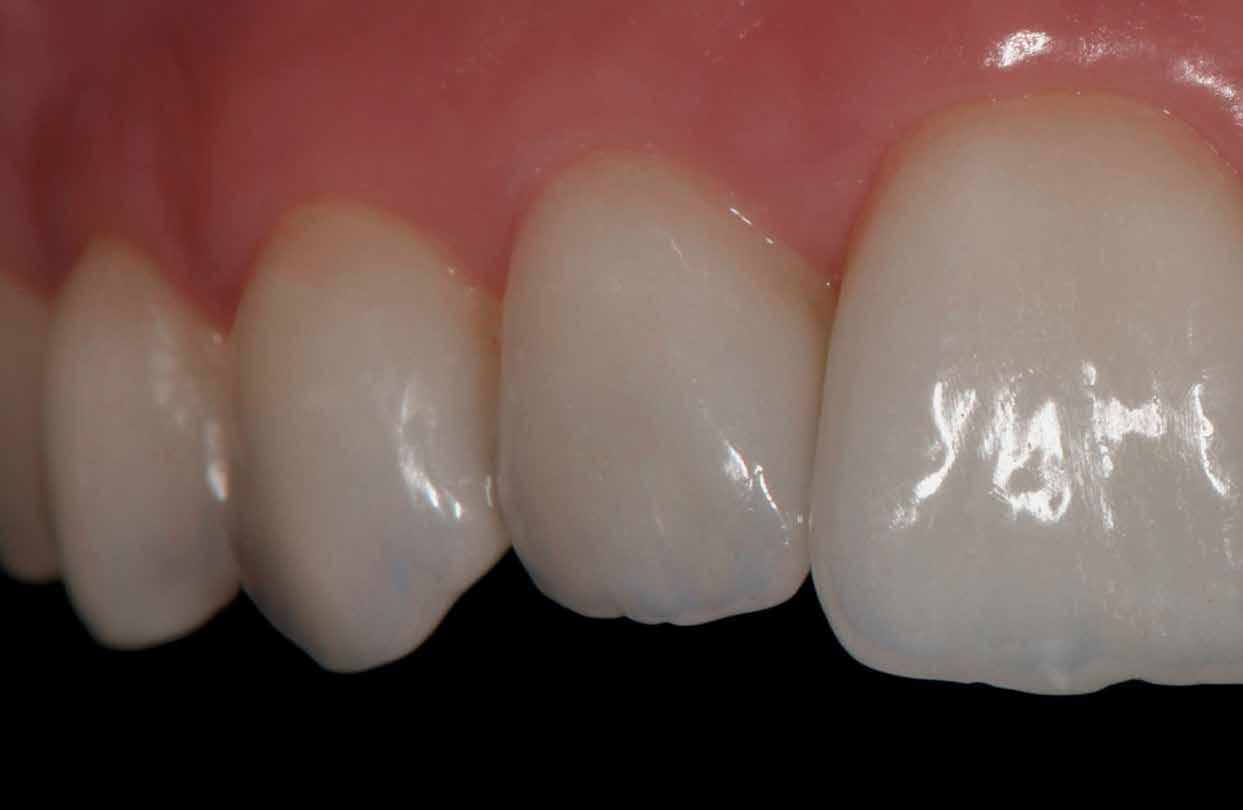

Végezetül részletfelvételek egy másik ragasztott hídról, amely hasonló módon készült, hat hónappal a behelyezés után (42–43. képek)

A hídtag enyhe mozgathatósága miatt az íny stimulálva volt. Ezzel a vérellátás további segítséget kapott, ami a lágyszövet kiváló adaptálódását hozta magával.